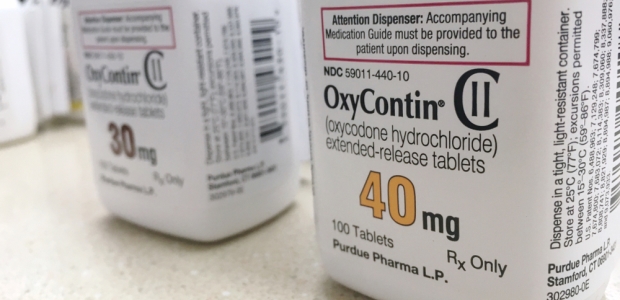

The Ohio Bureau of Workers' Compensation will no longer pay for Oxycontin or generic sustained-release oxycodone tablets for workers who suffer on-the-job injuries on or after June 1, 2019. Injured workers who are currently on those medications will have until Dec. 31 to discontinue their use or switch to a different product on the state agency's formulary.